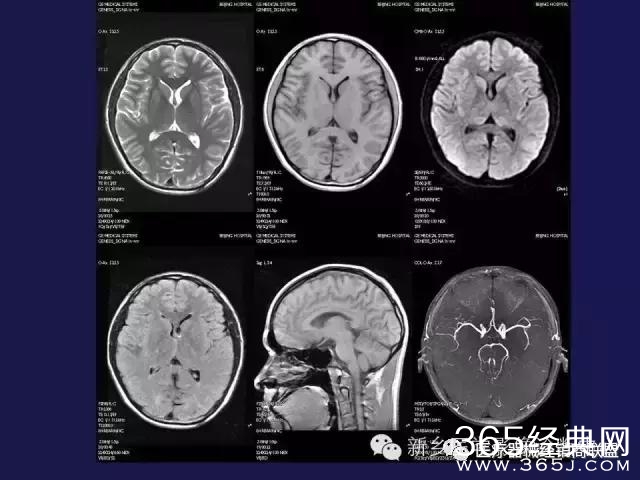

CT、MRI很难?NO,今日我们一起来学习一下如何读CT、MRI!

内行看门道: